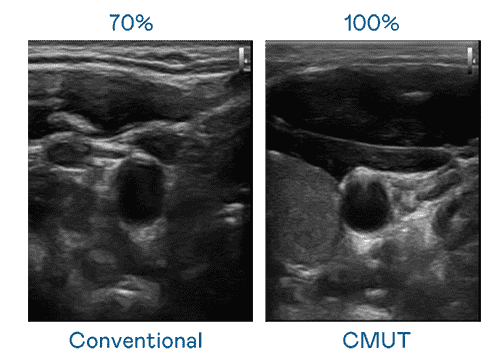

CMUT 技术是一种用电容式微机电元件来产生超音波讯号的技术。。与传统 PZT 压电式技术相比,,CMUT 频宽增加 30%,,,更宽频的超音波讯号让影像解析度大幅提升,,是实现高影像品质医疗超音波扫描、、、、促进精准医疗发展的关键技术。。。

超音波影像的解析度高低,,首先取决于探头能发出的讯号频宽。。尊龙集团 CMUT 可提供高清晰的超音波讯号,,,,提供高频宽、、、、高灵敏度、、、影像纹理细节更高的超音波影像,,,,协助医护人员缩短影像判读时间及利用精准的医疗影像进行诊断。。